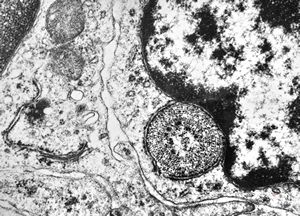

M,41y. | ribosome-lamella complex in tricholeukocyte -hairy cell leukemia, spleen

M,41y. | ribosome-lamella complex in tricholeukocyte -hairy cell leukemia, spleen